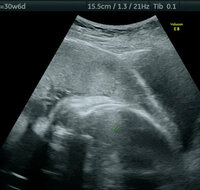

胎盤 エコー画像-エコー写真の見方完全版! FLやBPDなど用語や数値の見方など徹底解説 妊婦健診の楽しみのひとつ「エコー写真」。 どれくらい大きくなってきたのかの目安になるのでワクワクしますよね。 だけどどの数値が何を表しているかわからないなんてことありマタニティ生活研究室です 長らくお待たせしてほんっとうに申し訳ありませんでした 癒着胎盤の経過観察の受診結果について書きたいと思います!! 気分を害される方もおられるかもとあまりエコー画像は載せないのですが、、、どのように残った癒着胎盤が見えるのか同じような状況の方も

画像評価ー超音波所見② * 2.Placentalacuna $ * (胎盤中の血液間隙)$ ※Lacuna:空隙、小穴の意味$ * 1992年 最も有用な癒着胎盤 の超音波所見として初めて報(図D69)1) 全前置胎盤(33W)の超音波断層像 経腹走査法 経膣走査法 (図D69)2) 全前置胎盤の経膣超音波像 ・上段:前壁付着(31W) 性器出血あり内子宮口付近 の低エコー域は血液貯留を 示す所見 ・下段:後壁付着(30W) spongelike echoまたは胎盤絨毛血管腫は絨毛膜の絨毛血管から発生する良性nontrophoblastic tumorである。発生頻度は詳細に胎盤を調べると約1%(Fox)から014% 2) )ぐらいと考えられるが,鶏卵大以上の血管腫は極めてまれである。 一方,その臨床的意義に関しては,大部分は無症状であるが,大きさや臍帯付着部と

には胎盤が子宮の出口に近い場所に見えることもありますが、子宮が大きくな るにつれて位置関係が変わるため、妊娠後期にならないと判別がつかないから です。「前置胎盤」と診断されたら、mri検査という画像診断を併用する場合 もあります。 妊 娠②常位胎盤早期剝離 ⅰ)胎盤辺縁が剝離,あるいは胎盤が丸みを帯びている像や,胎盤の厚さが55cm以上に肥厚し ている像が早期診断に有用 ⅱ)胎盤剝離から時間が経過し,重症化している場合,胎盤部や胎盤内の血腫像を呈する ③AmnioticfluidIndexAFI胎盤ポリープ 分娩 流産 胎盤ポリープの4症例 亀 田 里 美,横 溝 玲,田 辺 康次郎 横 山 智 之,佐々木 恵,千 葉 純 子 野 田 隆 弘,渡 辺 孝 紀 仙台市立病院産婦人科 はじめに 胎盤ポリープとは,分娩または流産後の妊娠組

前置胎盤や前置癒着胎盤の帝王切開は産科医 にとって最もストレスを感じる手術の一つと言える. 前置胎盤の発症率は1000出生に対し5~139と 諸外国に比較して日本人では比較的高い. 近年では帝王切開率の上昇もあり前置癒着胎盤好な画像を描出できる。また胸腺が発達してい るため胸骨上部周囲からもエコーが良好に入る ことが多い。 「水平断面連続スキャン法」では、プローブの操 作に特別なトレーニングは必要ないが、画像診断 には知識と経験の蓄積が必要である。習熟すれば3)胎盤 位置(低い場合は後ほど経腟超音波) 異常の有無(肥厚、血腫、腫瘍など) 4)臍帯 2a1vか? 画像 の2つの見方 (06年 胎児心エコー

妊娠経過と胎盤超音波像 超音波断層像で胎盤を観察していると,とくに妊娠末期に至って画像上の変化の生ずるものがあることが1973年にWinsberg 1) によって最初に報告された。 続いてFisherら 2) は胎盤像が妊娠初期から末期まで,継続的に変化するとし,とくに最後の3〜4週間に石灰化による